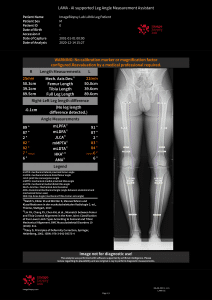

Dr. Richard Ljuhar:IB Lab is aiming to disrupt the way bone and joint diseases are currently being diagnosed. Technologies such as AI-supported software offer a novel way to translate imaging data into structured health information. IB Lab has developed (and certified) a unique MSK-analysis-focused digital workflow platform named IBLAB ZOO. Our deeptech technology is based on state-of-the-art image recognition algorithms and AI, trained on data sets extracted from an accessible image pool of 10 million medical images of various formats. The initial focus of our MSK platform has been on 2D X-ray modules for the knee, hip, hand and spine. The structured information extracted from imaging data enables us not only to disrupt the current workflow by providing standardization and increasing diagnostic accuracy, but also to create new insights into the prediction of disease onset and treatment outcomes.

Dr. Richard Ljuhar: Targeted treatment options ensure shorter periods of suffering, quicker recovery by applying objective assessment/progression measurements and prevention/delay of disease progression, leading to better outcomes. Enhanced and well-structured reports ensure ideal patient communication. MSK diagnoses are often time-consuming and subjective. IB Lab supports radiologists and orthopedists in their daily decision-making with standardized, fast and resource-effective AI-based software solutions for automated measurements on radiographs that accelerate the workflow and improve the time and quality of patient care.